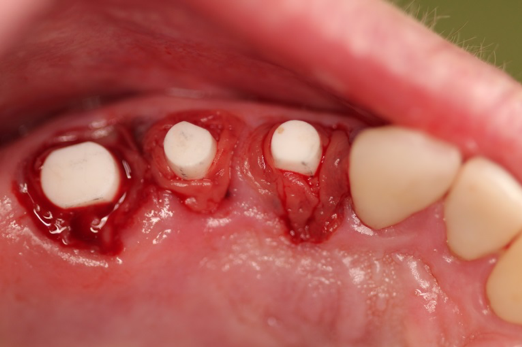

Fig 12. Ceramic implants placed and sutured.

Figure 12

Figure 10 through Figure 13 show the preoperative x-ray and the sequence of beginning with healed sites through the surgical placement of the implants. The implants were protected by an Essix-style wound-protection removable retainer for approximately 12 weeks. After the integration phase, the implants and the natural dentition were prepared using traditional crown-and-bridge high-speed diamond and zirconia cutting burs to remove decay and existing restorative materials, to complete and refine the natural-tooth structures to receive full-crown coverage, and to prepare and refine gingival margins of the zirconia implants where needed.